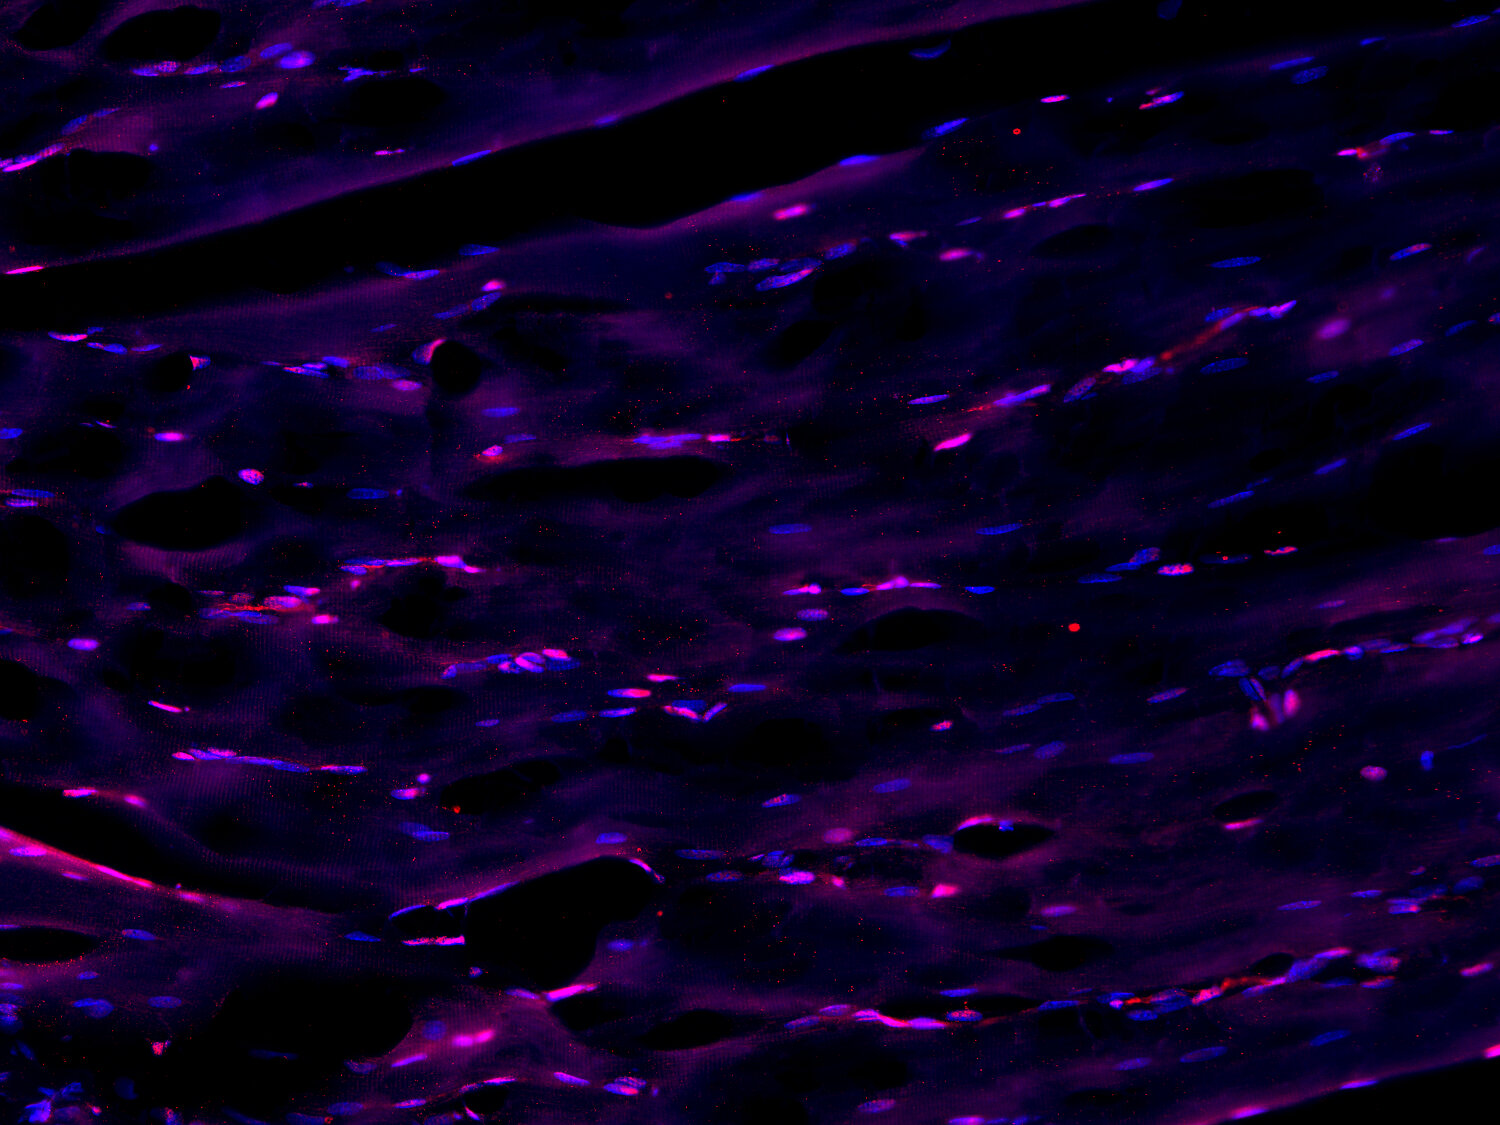

IHC: Antigen retrieval with citrate buffer pH 6 is required for immunohistochemical staining in mouse muscle section.